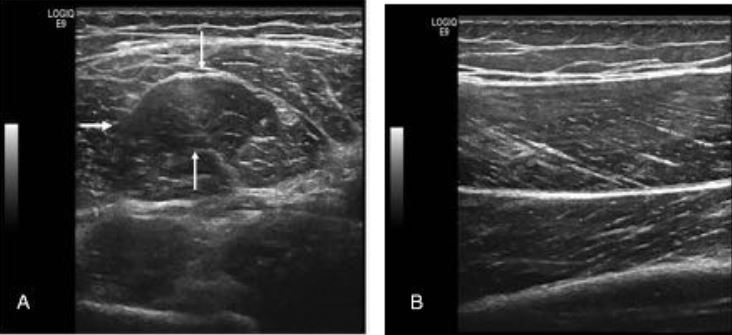

-Describir los principales hallazgos ecográficos de las lesiones musculares.

Las lesiones musculares agudas constituyen una patología frecuente, no sólo asociadas a la práctica deportiva sino también a las actividades cotidianas, generando de forma creciente la necesidad de atención sanitaria y su valoración con pruebas de imagen.